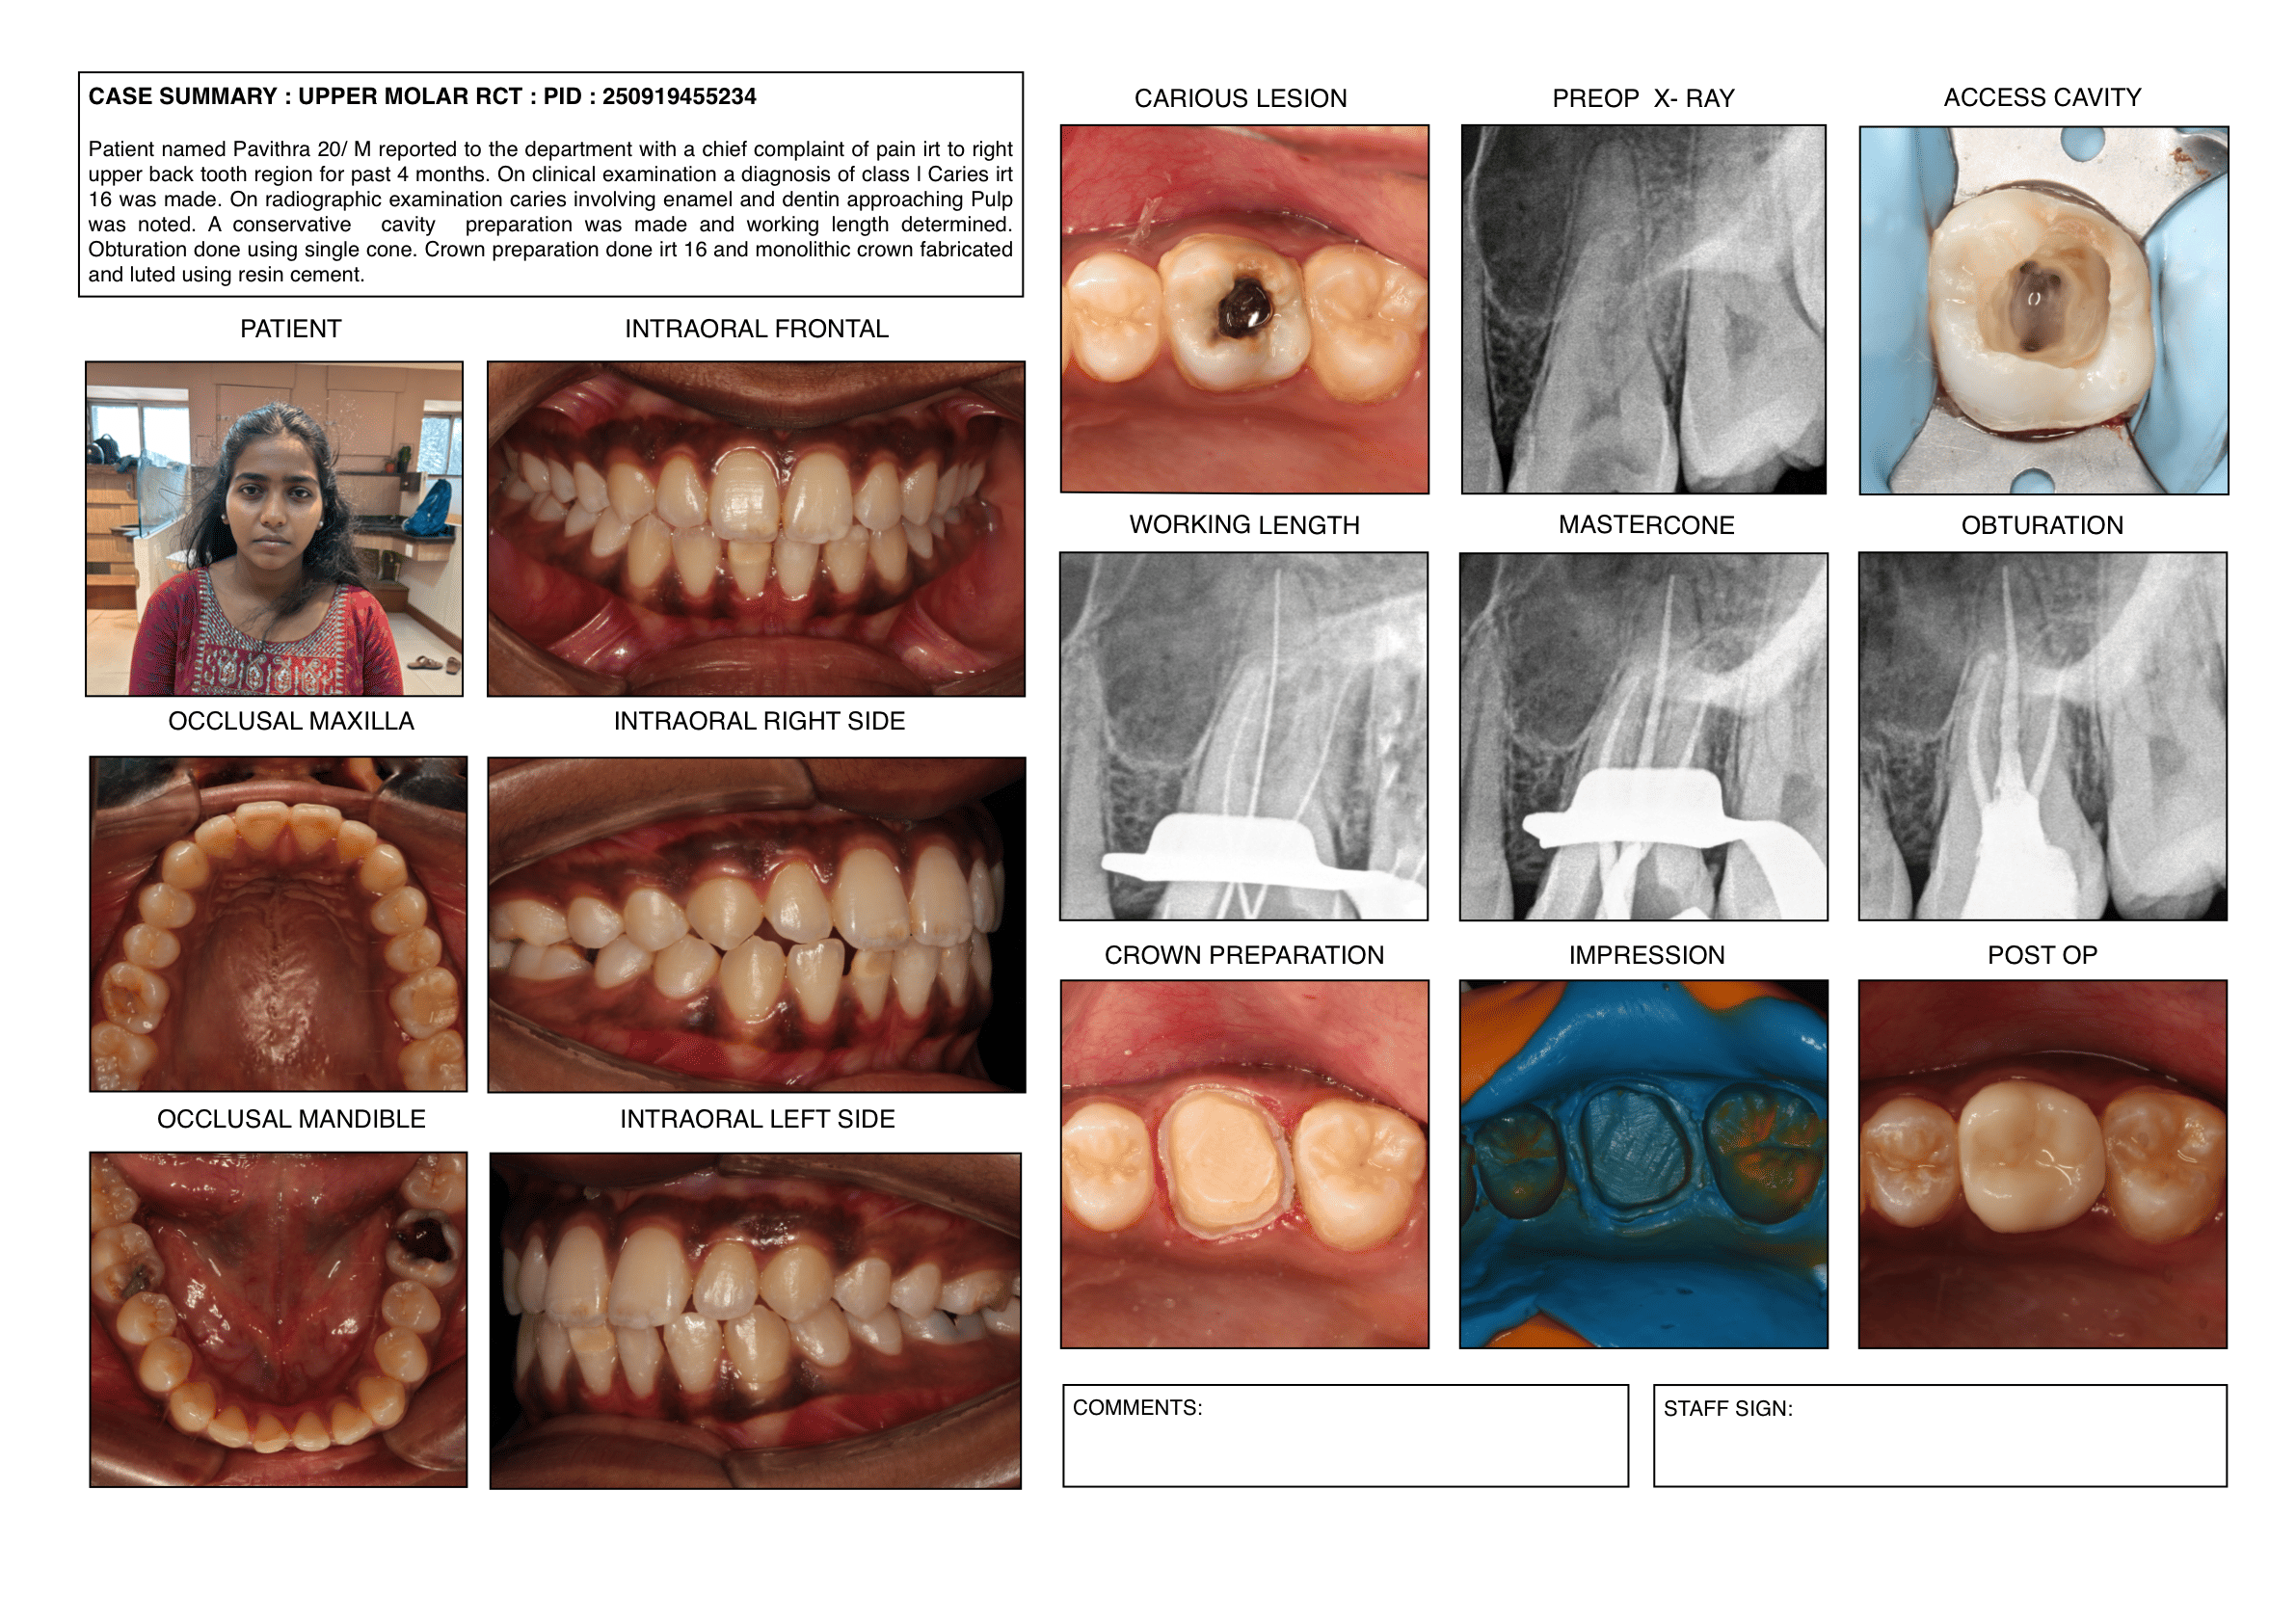

Endodontic cases